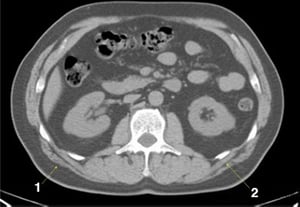

CT-Scan von Abdomen und Becken mit normaler Anatomie ohne Kontrastmittel (Folie 13)

1 = V. mesenterica superior; 2 = A. mesenterica superior.

© Springer Science+Business Media